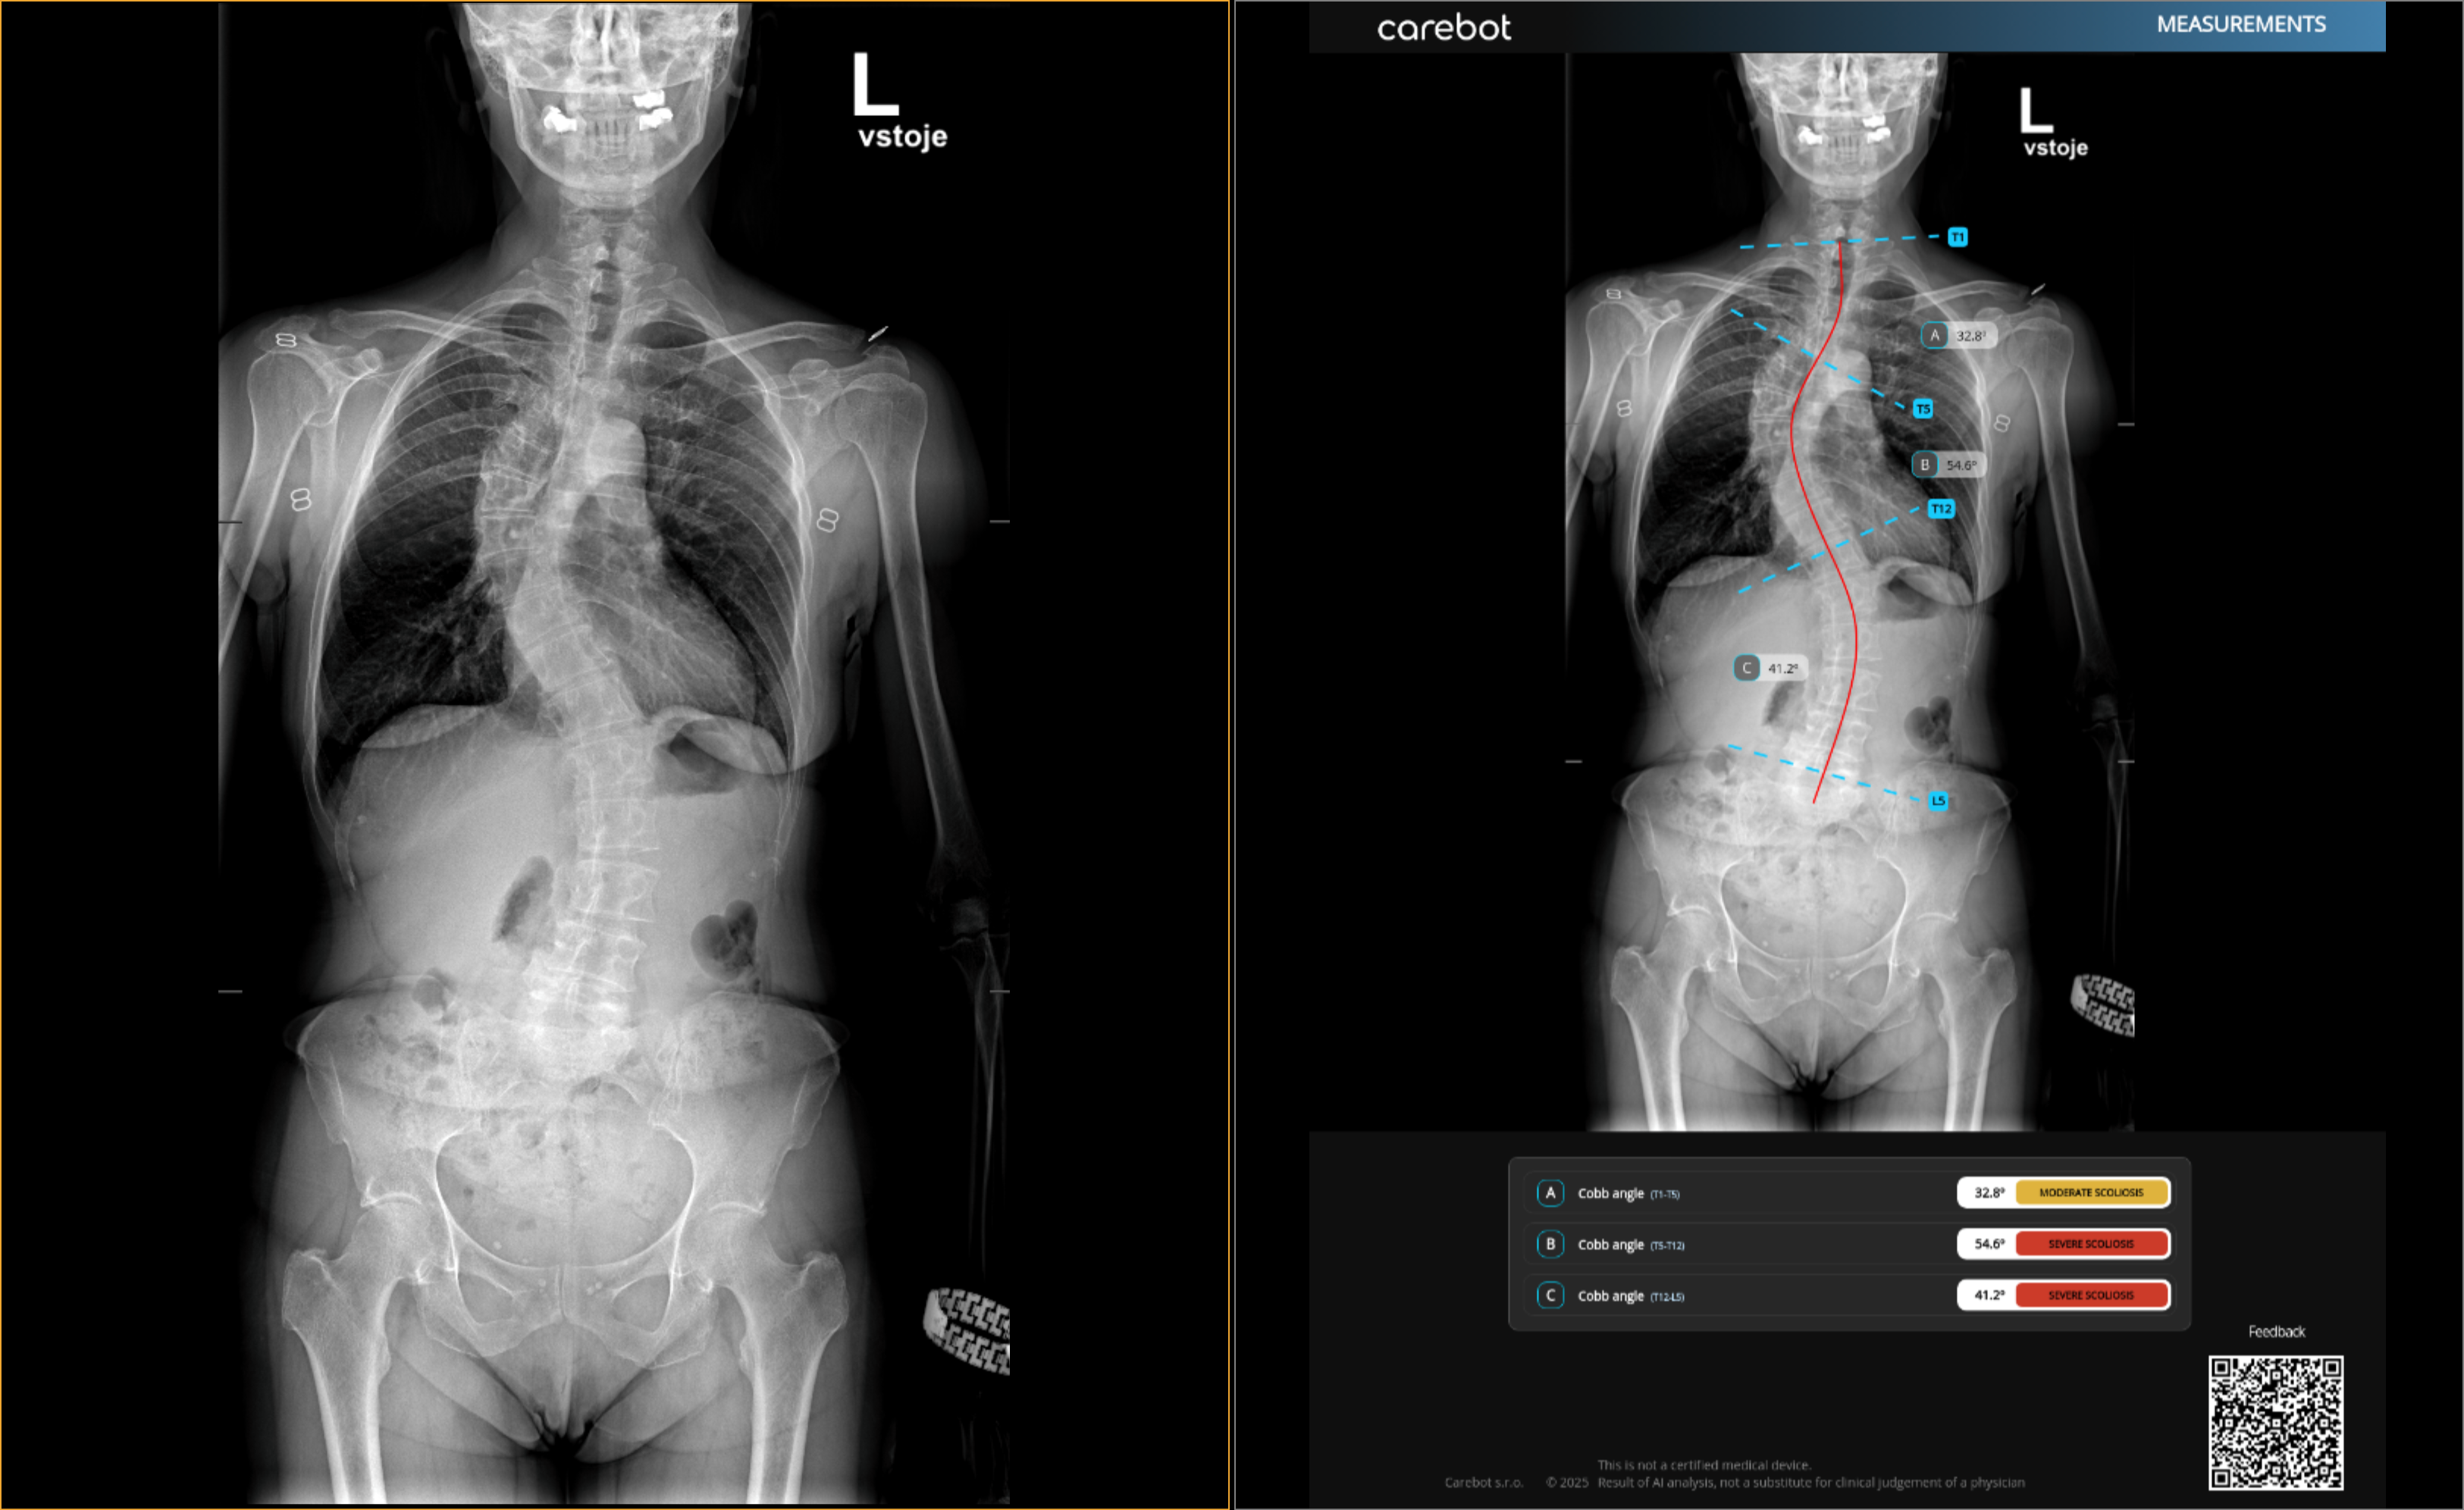

Multi-Centre Validation of a Deep Learning Model for Scoliosis Assessment

Skolióza postihuje přibližně 2–4 % adolescentů a rozhodnutí o léčbě závisí na přesném měření Cobbova úhlu. Ruční hodnocení je pomalé...